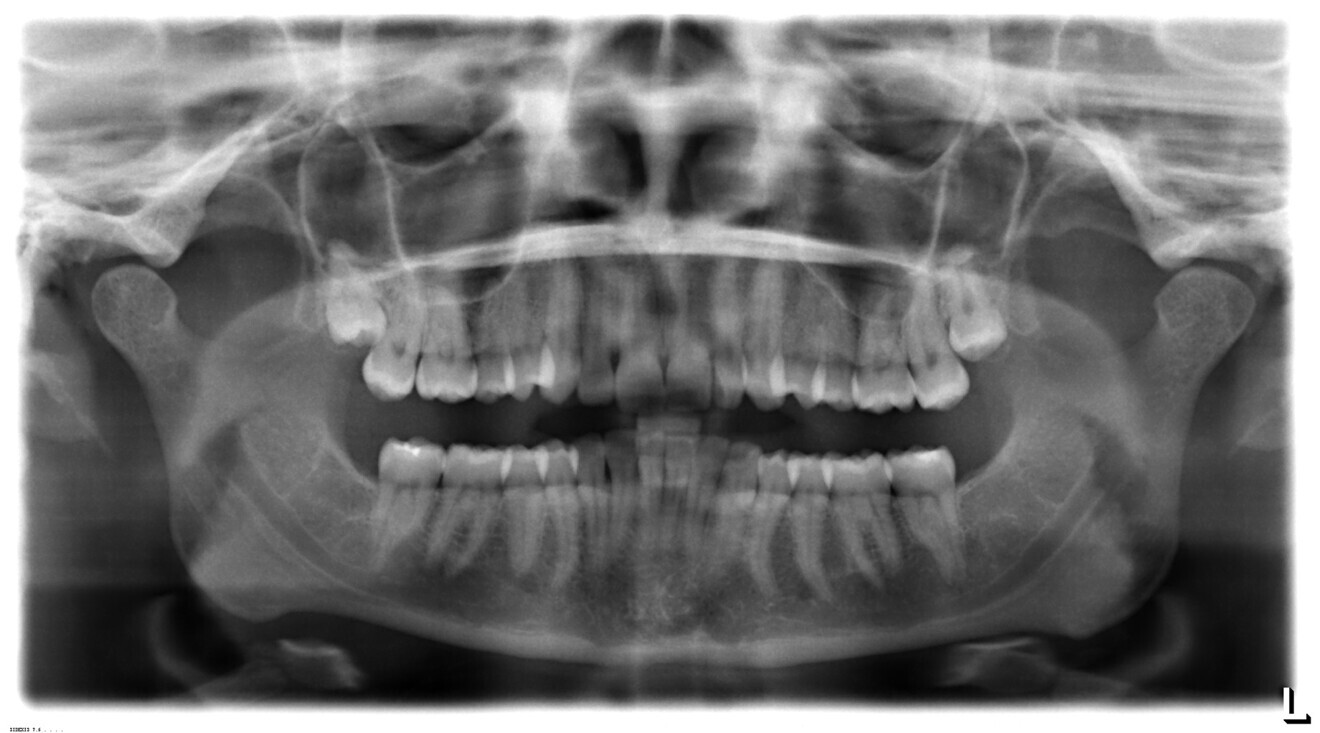

Fig. 2: Panoramic radiograph.

A 35-year-old female patient presented with an increased overbite, an increased overjet of 7 mm, and a bilateral Class II molar relationship, exhibiting a three-quarter unit distal occlusion on the right and a half unit distal occlusion on the left (Figs. 1–3). Orthognathic surgery had previously been recommended owing to the Class II skeletal relationship evident in the cephalometric analysis, but the patient declined this option.